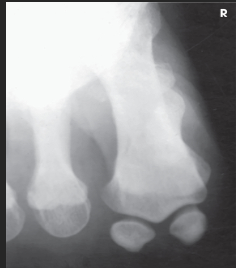

Name this projection.

AP oblique toes

State the degree and type of rotation used.

Medial rotation 30-45 degrees

Which aspect of the foot rests on the IR?

Medial aspect

Where does the CR enter?

Perpendicular to 3rd MTP joint

When radiographing the 1st-2nd toes, which oblique should be used?

Medial (rotate on medial/unaffected side)

When radiographing the 4th-5th toes, which oblique should be used?

Lateral (rotate on lateral/affected side)